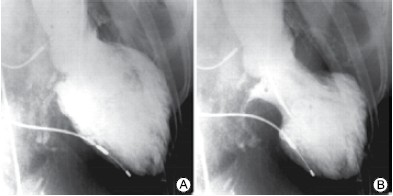

Mulher, 75 anos, apresenta dor torácica de forte intensidade após o falecimento do marido. É levada ao serviço de emergência onde eletrocardiograma mostra supradesnivelamento do segmento ST de V1 a V6. Encaminhada para hemodinâmica que mostra os seguintes achados:

Coronárias:

Enunciado 3281746-1

Ventriculografia:

Enunciado 3281746-2

(Arquivo pessoal; imagens usadas com autorização)

Assinale a alternativa com o diagnóstico correto.